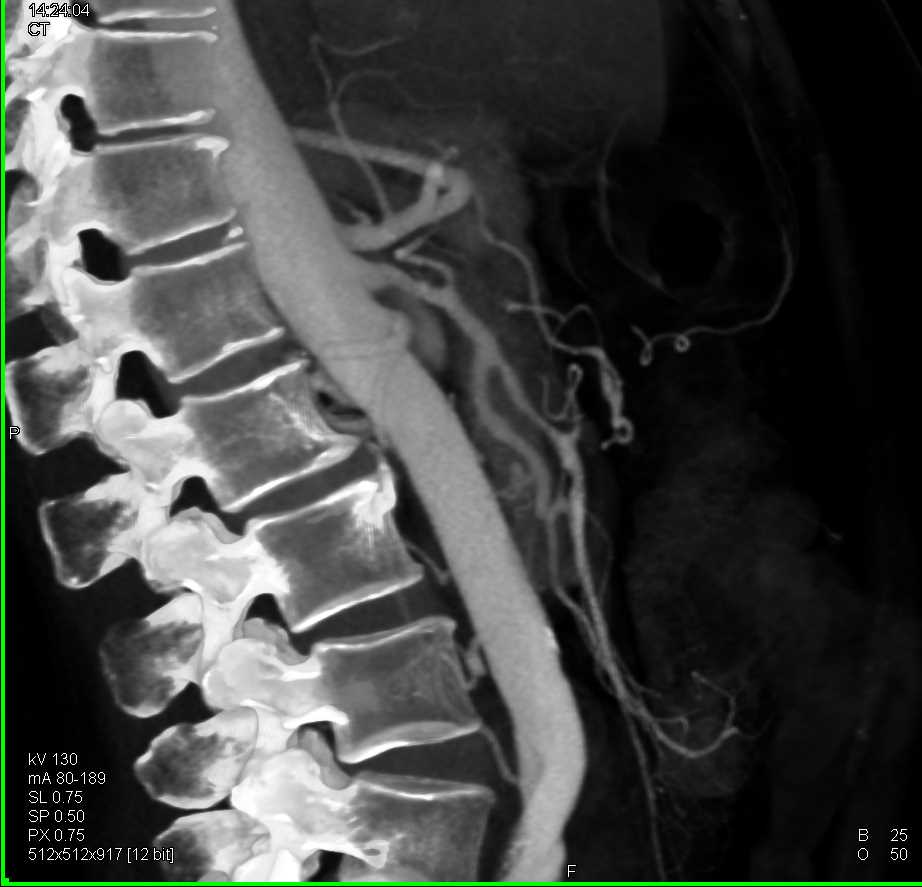

Neuroendocrine Tumor Body of Pancreas